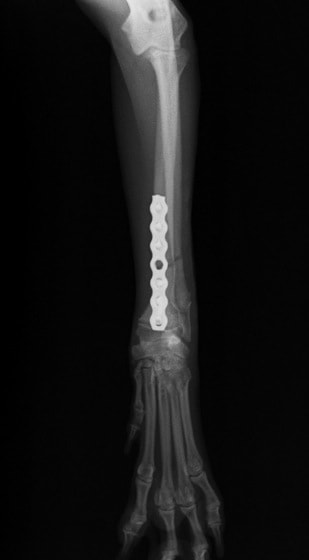

ペルシャ猫 11ヶ月齢 雄

他院にて左大腿骨遠位の成長板骨折(salter-harrisⅠ型)が認められており、治療相談を目的として来院。当院にて、キルシュナーワイヤーを用いたピンニングにより骨折部位の整復を行いました。術後の経過は良好で、現在も経過観察中です。

術後レントゲン

Arthrex社のターゲティングデバイスを用いてピンニングの位置を調整することで、確実な固定を行っています。当院ではこの手術器具以外にも、人の手術にも使用される様々な器具を導入し、手術精度を高め、また医療メーカーと新しい器具の開発、試作にも取り組んでおります。